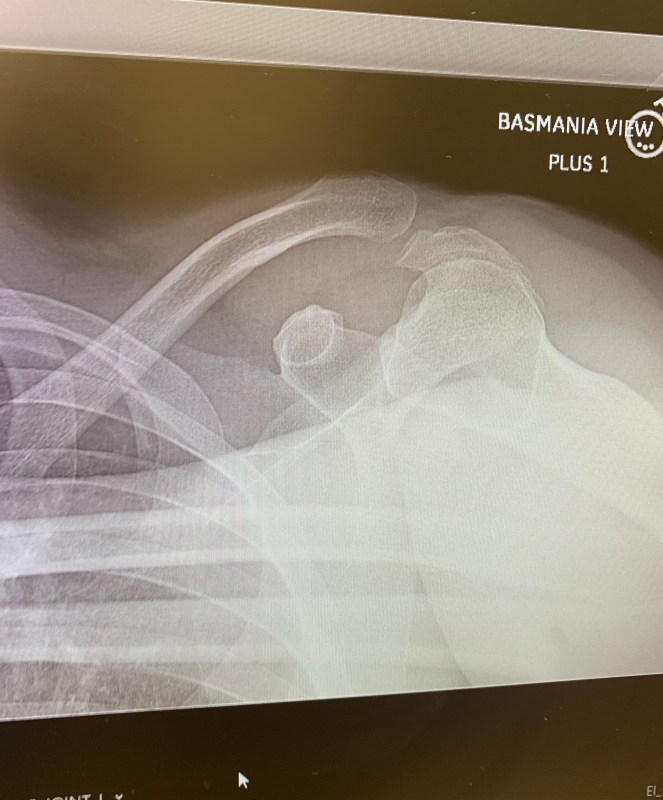

Our old man editor finally gets his wayward clavicle put back into place today at the Hospital For Special Surgery. Frankly, we’ll be glad when this is all over. For the last five days since his “cat”-astrophic crash, all his emails, and half of his published stories, have been filled with the most bizarre typos, mostly because he is dictating everything on his iPhone — and Siri doesn’t speak Grizzled Tabloidese (admittedly, a dying language).